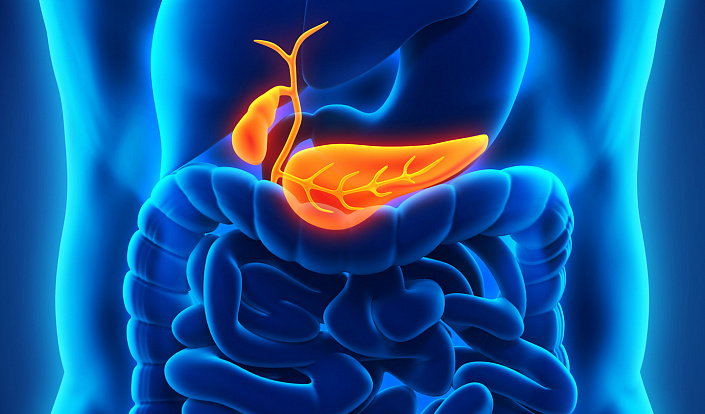

Поджелудочная железа

В верхнем отделе брюшной полости располагается ещё одна эндокринная железа — поджелудочная. Эта железа представляет собой продолговатый орган, расположенный между селезёнкой и двенадцатиперстным отделом кишечника, длиной в среднем от 12 до 30 сантиметров в зависимости от возраста и индивидуальных особенностей человека. В отличие от большинства эндокринных органов, поджелудочная железа вырабатывает не только гормоны. Здесь также синтезируется поджелудочный сок, необходимый для расщепления пищи и нормального метаболизма. Благодаря этому поджелудочная железа относится к смешанной группе, которая выделяет синтезируемые вещества и в кровь, и в пищеварительный тракт.

Круглые клетки эпителия (островки Лангенгарса), локализованные в поджелудочной, обеспечивают организм двумя пептидными гормонами — глюкагоном и инсулином. Эти вещества выполняют антагонистические функции: попадая в кровь, инсулин снижает уровень содержащейся в ней глюкозы, а глюкагон, наоборот, повышает его.